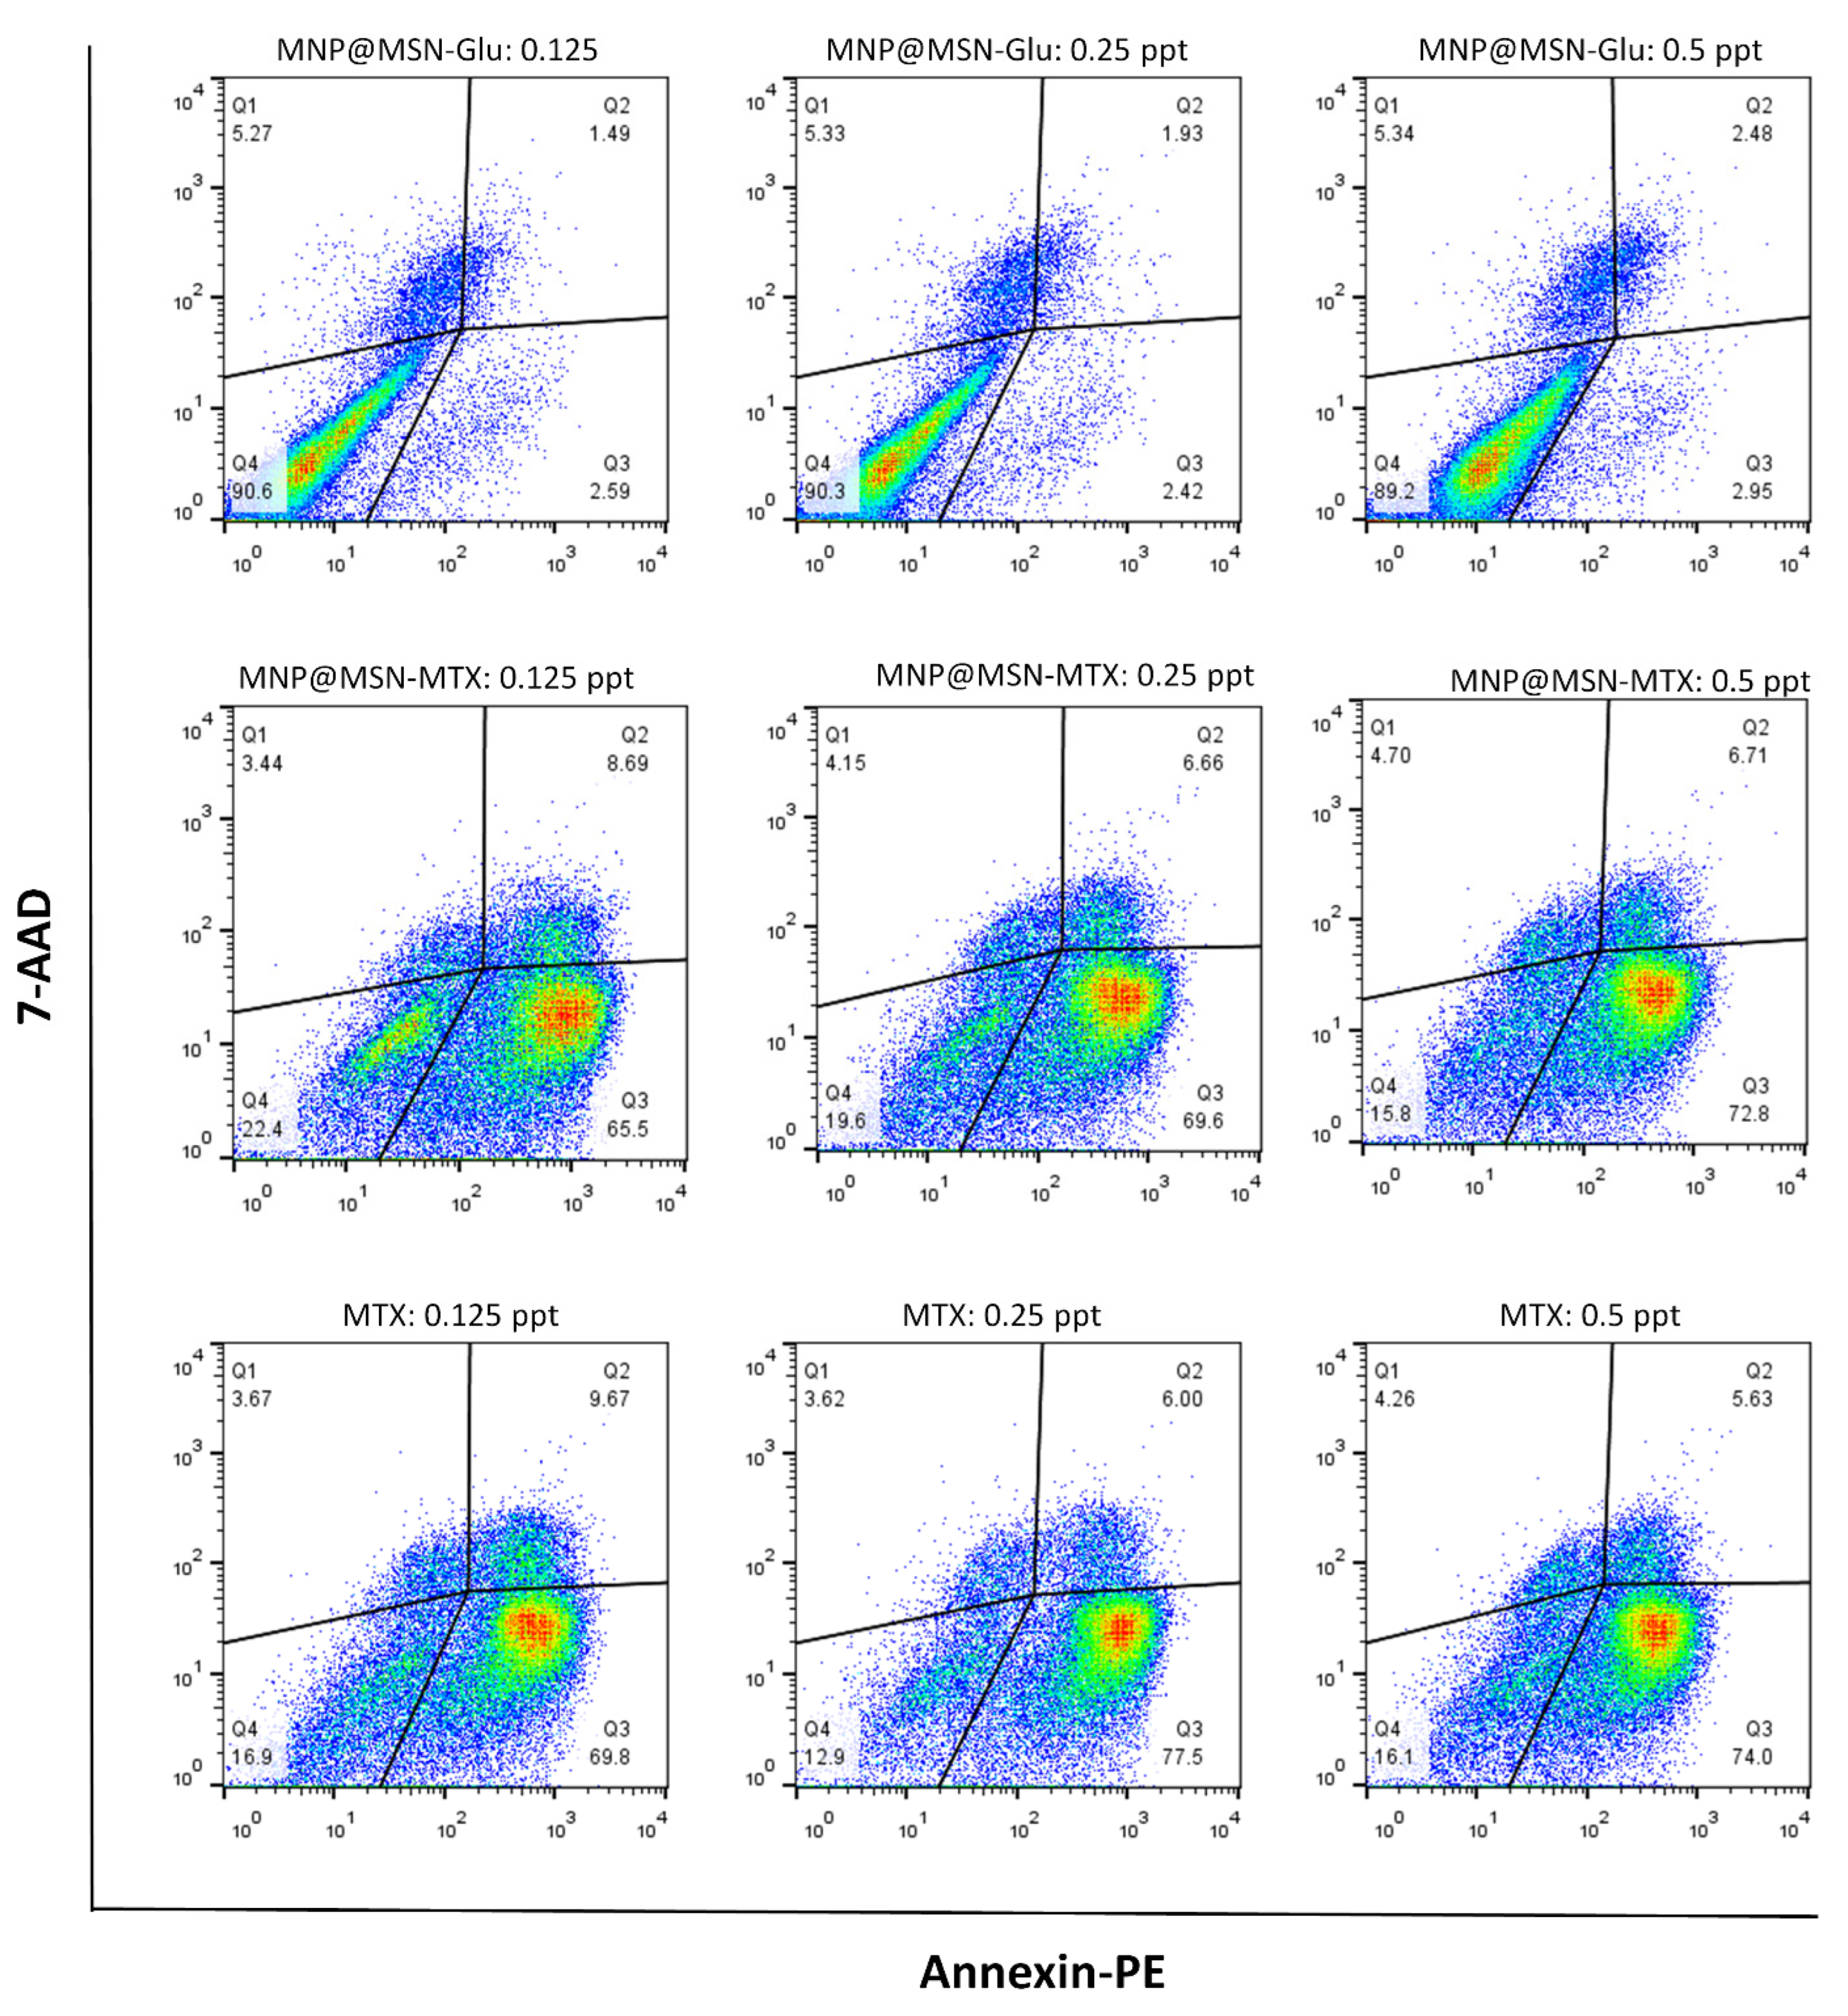

2.9. Apoptosis Assay

3.4. Cytotoxic Effect of MNP@MSN-Glu on 4T1 Cell Line